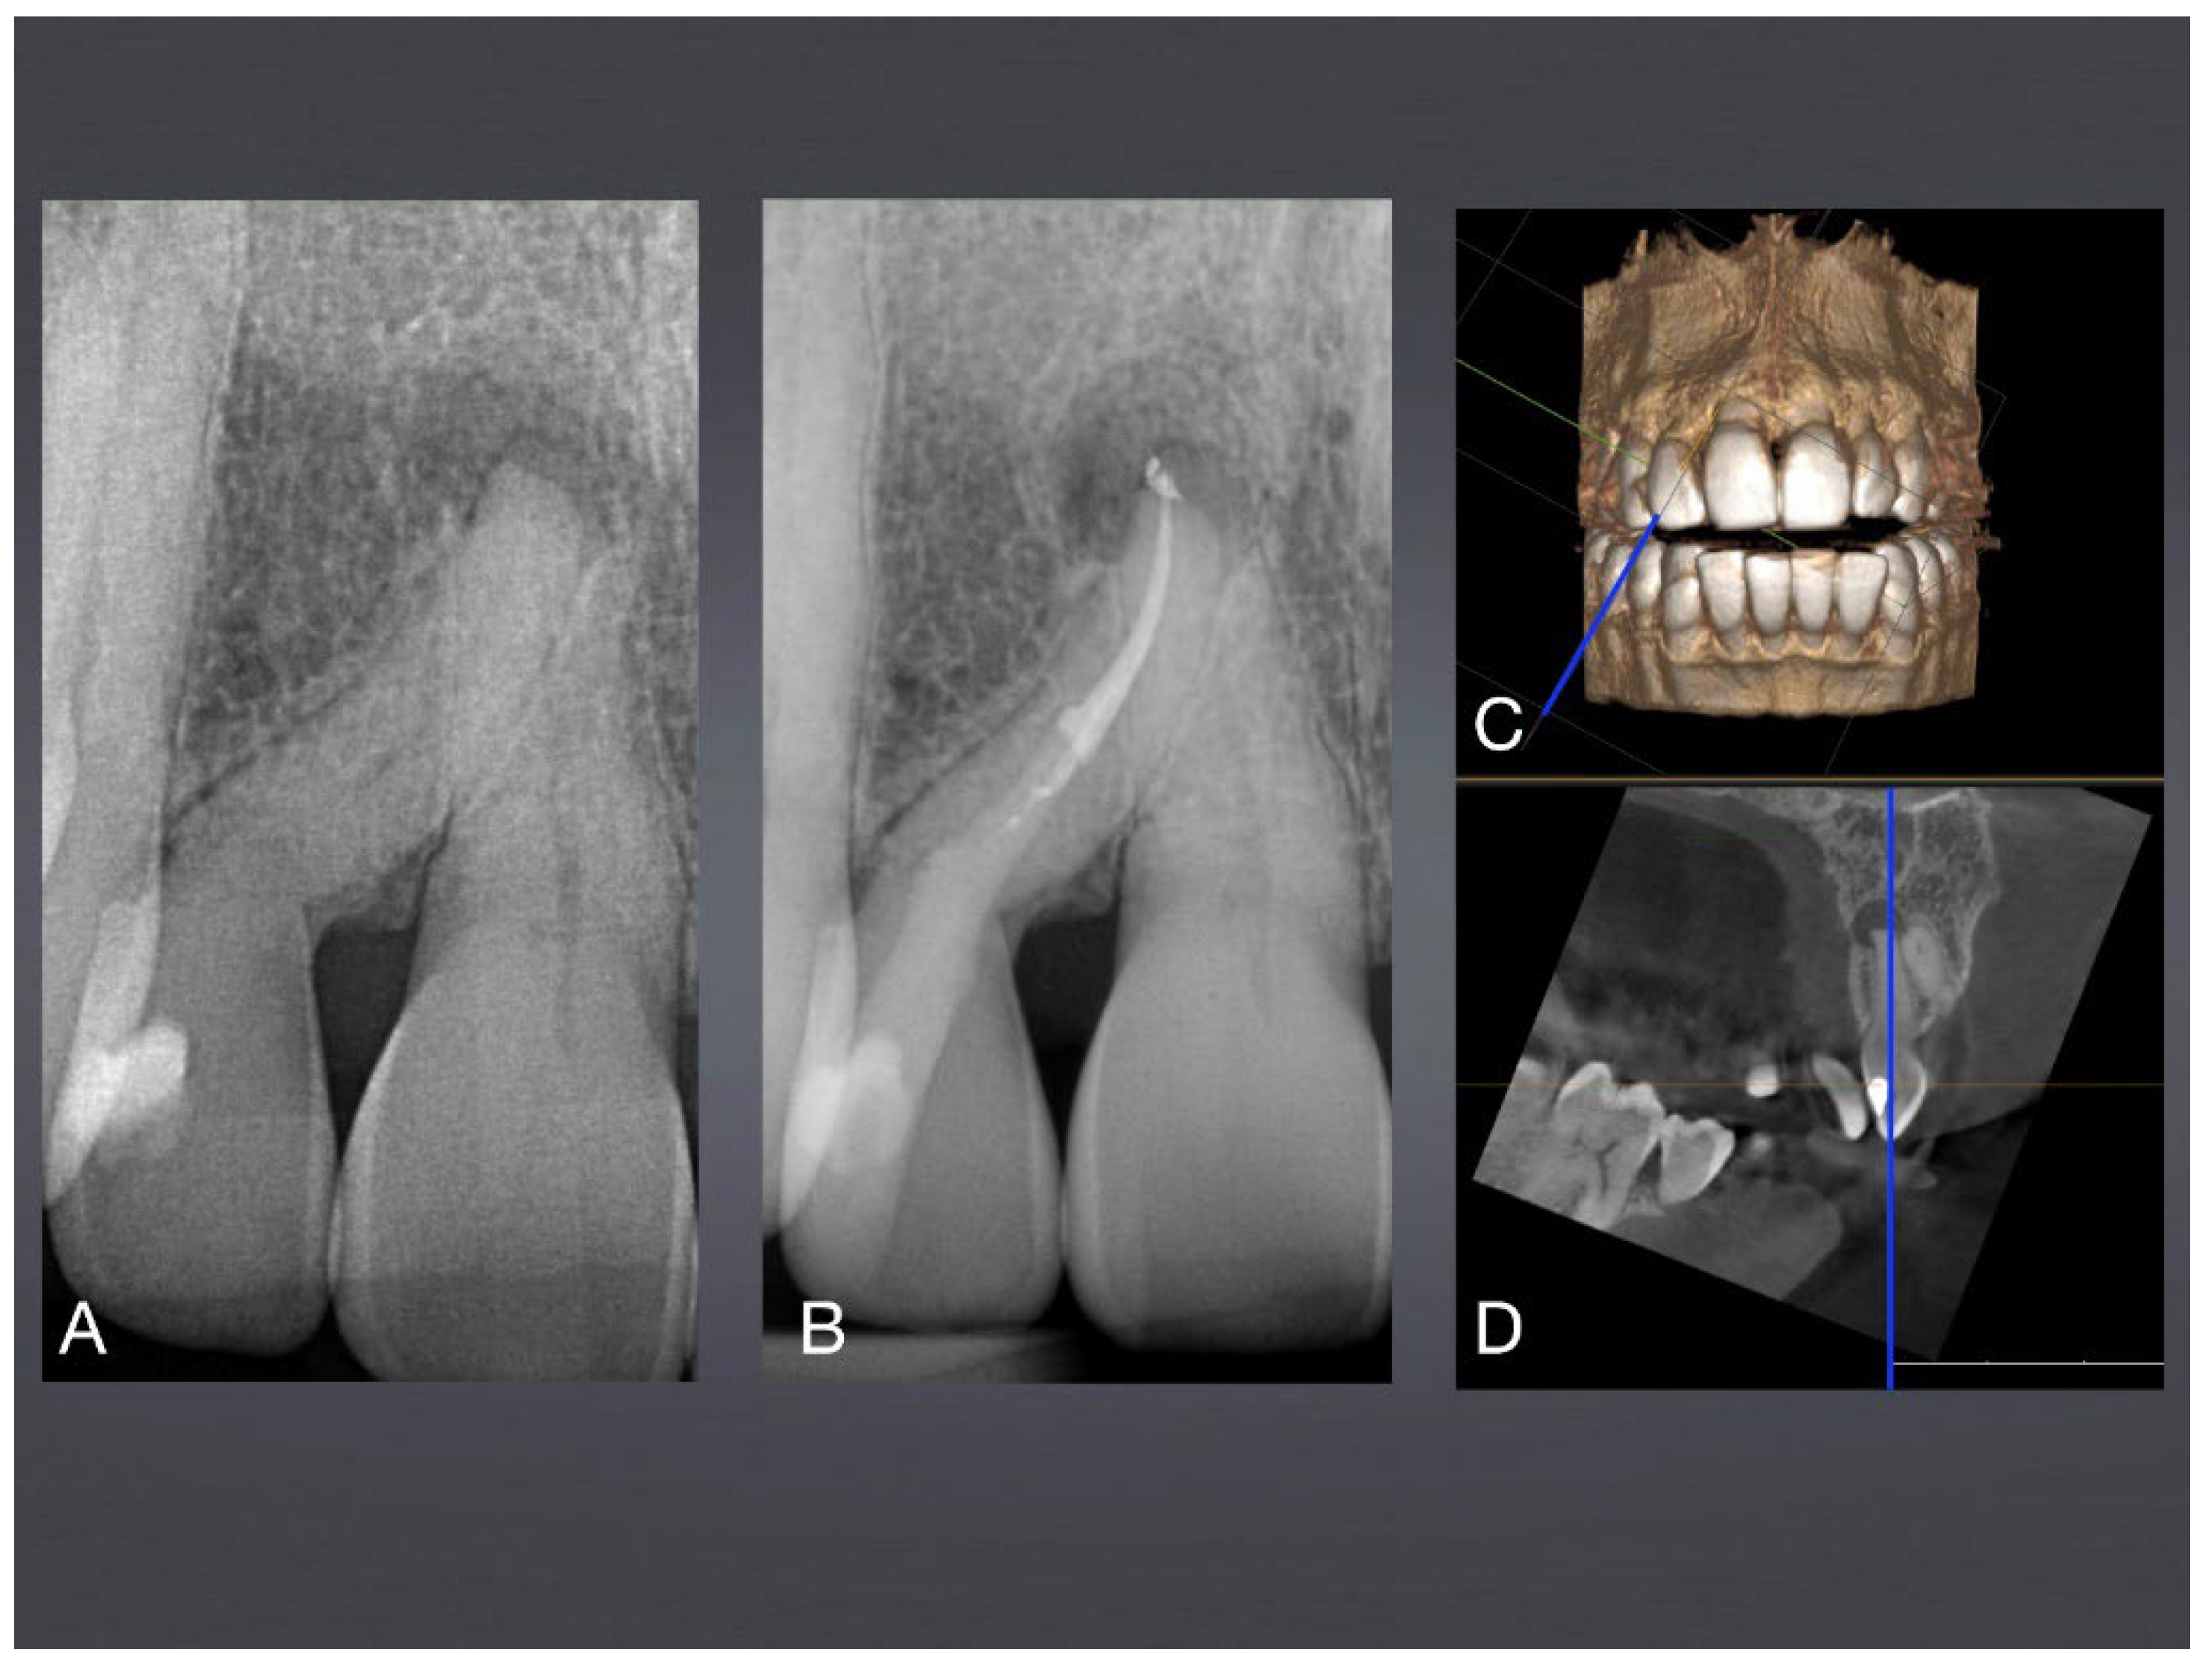

Figure 5. Tooth anomaly of mandibular permanent incisor with dilaceration due to trauma at age of 6 years, consequently obliterated pulp chamber and outer half root canal. A: Baseline X-ray with posterior profound caries lesion and apical periodontitis. B: final X-ray after root canal treatment and fiber post stabilization. C+D: Planning of approximal access cavity with CBCT imaging (blue line).